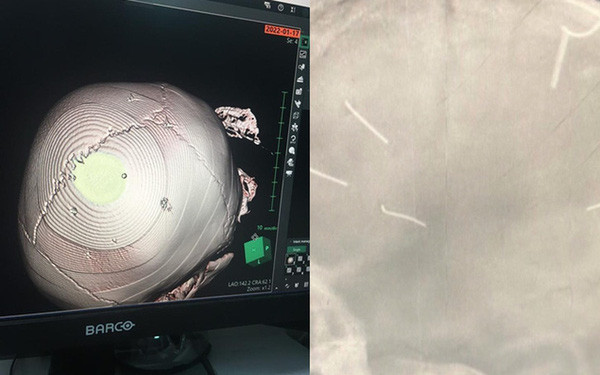

| Bé A. có 9 vật thể giống đinh trong hộp sọ khi nhập viện. |